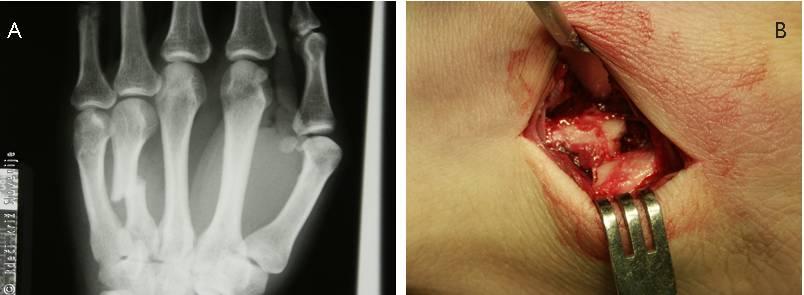

Slika 25

A – RTG slika prečnega zloma dlančnice.

B – Prečni zlom 4. dlančnice med operacijo.